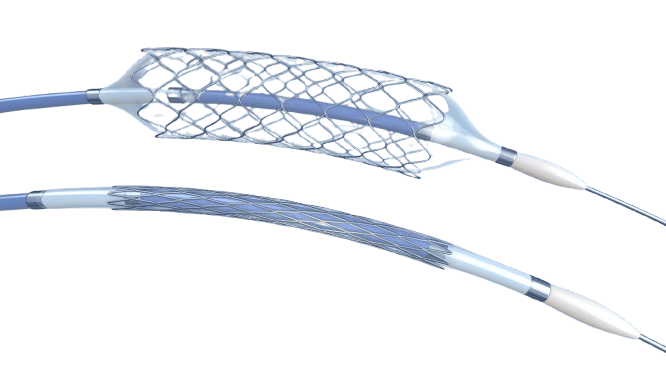

Balloons

HOOP Company specializes in the development and manufacture of advanced medical balloon components for the global medical device industry. The company offers a diverse range of balloons, encompassing non-compliant (non-stretchy) and ultra-compliant (very stretchy) options in various shapes and sizes.

HOOP Company maintains a robust inventory of popular balloon materials, including Nylon, PET, Pebax, Polyurethanes, and TPEs, allowing for swift fulfillment of custom requirements. Their state-of-the-art robotic blow molding process can be optimized to achieve specific design targets, such as thin walls, high burst pressures, and compact crossing profiles, delivering truly custom balloon components within a short lead time.

The company can efficiently blow mold balloons using a wide range of medical-grade thermoplastic materials. HOOP Company is equipped to assist clients in selecting the appropriate polymer to enhance balloon performance and ensure seamless integration with medical devices and assembly processes.